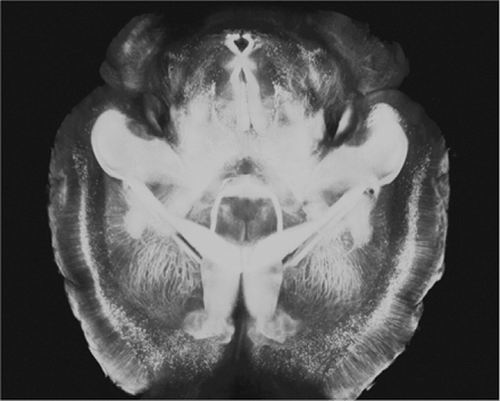

脑成像技术

2013年,大脑的一个新窗口被打开,有望从根本上改变实验室研究这种错综复杂的器官的方式,它被称为CLARITY。由于形成细胞膜的脂肪会散射光,CLARITY通过消除脂肪可以使大脑组织透明如玻璃,它使用一种凝胶取代脂质分子,同时能保持神经元、其他脑细胞及细胞器完整,从而使错综复杂的大脑结构呈现出来。

在以前试图建立透明大脑的技术中,各组织非常脆弱,但在CLARITY中,这些组织足够坚固,科学家可以多次将不同标记渗入其中,进而将其冲出,并使大脑重复成像。研究人员称,这种进步能够使计算一个特定大脑区域的神经元数量等任务的速度提升100倍。相比之下,传统的死亡脑组织成像方法变得无关紧要。不过,目前该技术局限于少量的组织:澄清4毫米直径的老鼠大脑仍需要大约9天。